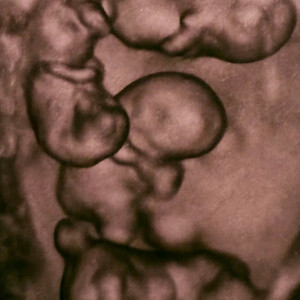

Однояйцевые четверняшки родились в роддоме № 17 в Санкт-Петербурге. Их появление на свет – это один случай на 15,5 миллиона родов, сообщили в медучреждении.

«Чудо в четвертой степени: в нашем роддоме родилась четверня! (...) На сроке 32 недели на свет появились четыре очаровательные сестренки. По расчетной статистике монохориальная - "однояйцевая" четверня – один случай на 15,5 миллиона родов. В стране не описано таких уникальных родов», – говорится в сообщении роддома в соцсети «ВКонтакте».

По информации РИА Новости, вес новорожденных девочек составляет от 1,36 до 1,64 килограмма, рост – от 37 до 41 сантиметра. По оценке специалистов родильного дома, это прекрасные показатели для рождения на таком сроке.